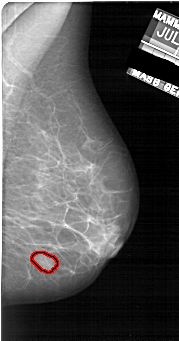

FILE: A_1922_1.RIGHT_MLO.OVERLAY

TOTAL_ABNORMALITIES 1

ABNORMALITY 1

LESION_TYPE MASS SHAPE OVAL MARGINS OBSCURED

ASSESSMENT 3

SUBTLETY 4

PATHOLOGY BENIGN

TOTAL_OUTLINES 1

BOUNDARY